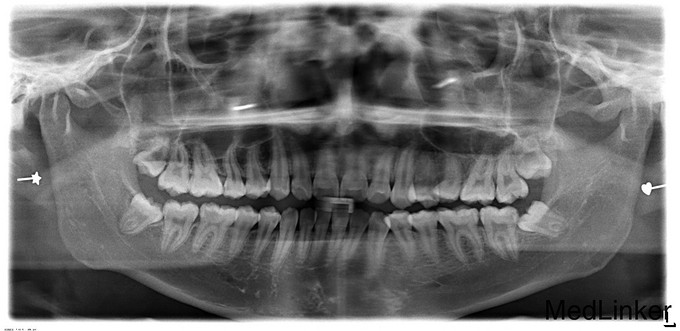

36远中颌面深龋洞,探质软,冷测剧痛,叩痛(-)无松动,牙龈无红肿 38可见部分牙冠,远中可见龈袋,牙龈充血,叩痛(-)

36牙髓炎 38阻生呀